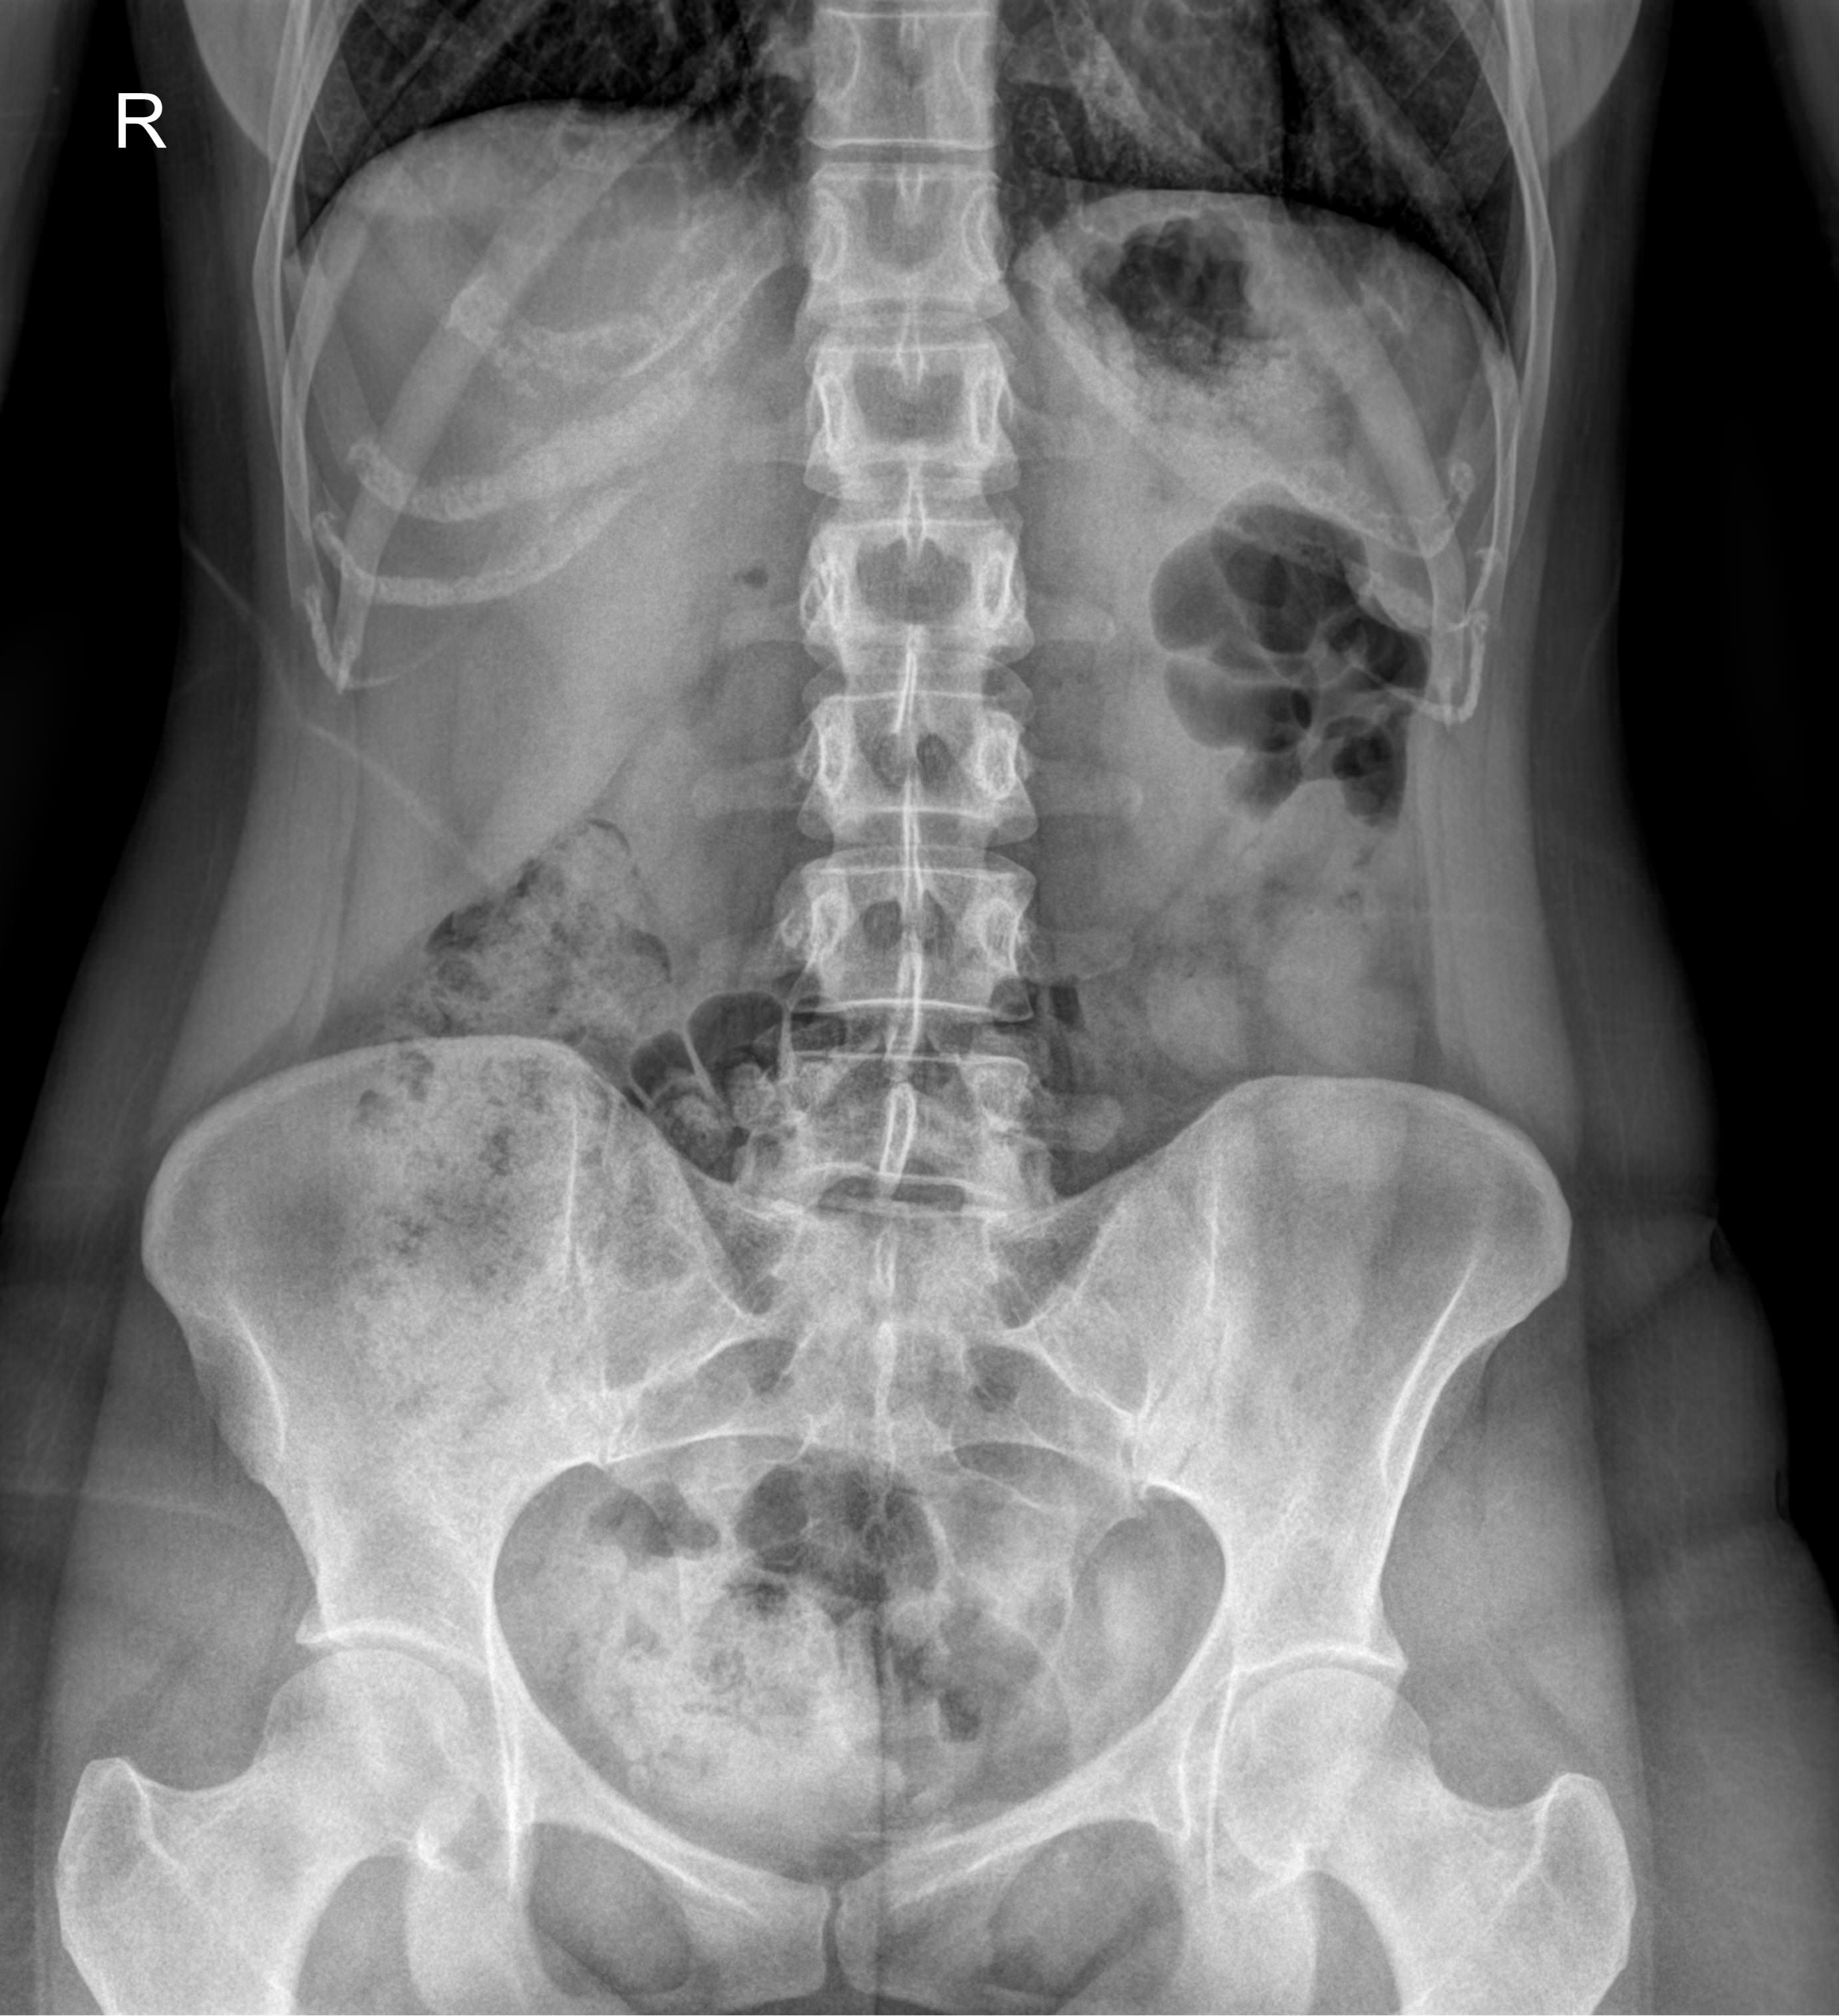

На рентгенограмме живота видны: газовый пузырь желудка, пневматизированные петли кишки, почки, печень, большие поясничные мышцы, диафрагма, нижние ребра, крылья подвздошных костей, боковые отделы брюшной полости. Этот вид диагностики чаще всего позволяет заметить не хроническую, медленно развивающуюся патологию, а экстренные изменения: нахождение жидкости и газа в местах, им несвойственных.

Внимание рентгенолога направлено на то, есть или нет на снимке:

- Свободный газ под куполом диафрагмы;

- Участки скопления газа в кишечнике;

- Горизонтальные уровни жидкости;

- Рентгеноконтрастные конкременты в области почек и желчного пузыря;

- Инородные тела.